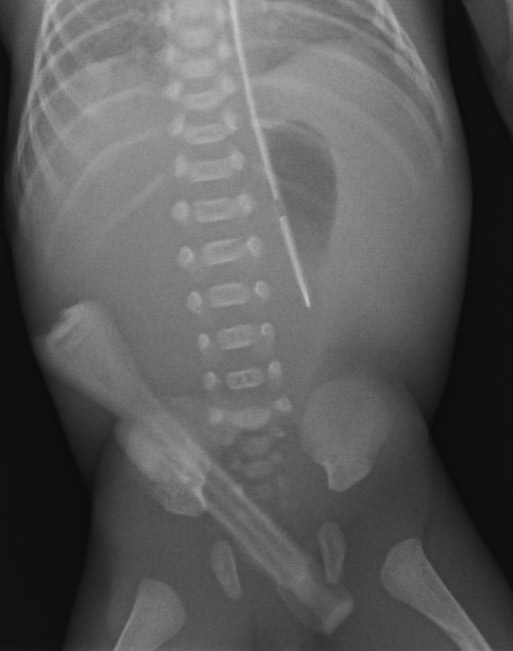

Smart Noise Cancellation (SNC) enables customers to lower radiation dose without loss in image quality. Performance validated in an internal study with 50% dose reduction from 220 IEC EI on average.*

* These statements were validated using Carestream CsI detectors in reader studies conducted by board-certified radiologists. Pairwise comparisons were performed between images at nominal exposure dose without SNC and at 50% reduced dose with SNC. The reduced-dose images included live patient images with simulated dose reduction, as well as images of human cadavers and anthropomorphic phantoms obtained using actual reduced-dose X-ray exposures. SNC performance was further confirmed using a CDRAD phantom. IEC EI values on average at nominal and reduced dose were 220 and 110, respectively.